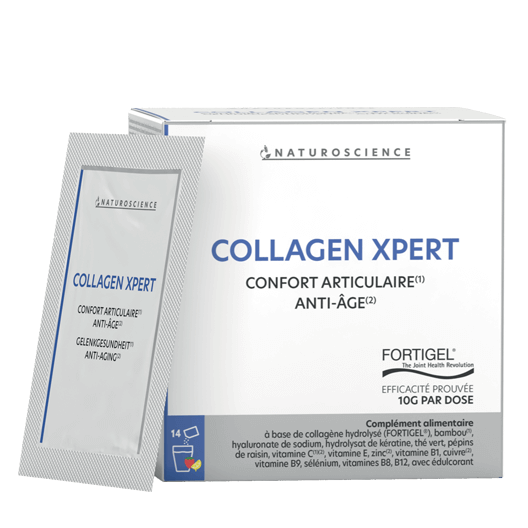

Pour remédier à ces désagréments, certains compléments alimentaires enrichis en acide hyaluronique (substance naturellement présente dans l’organisme et qui assure la bonne motricité des articulations grâce à la qualité des cartilages) ou grâce à l’association judicieuse de certains extraits de plantes, permettent de conserver la motricité des doigts. Ces associations de plantes et de minéraux agissent directement sur la qualité du cartilage et évitent les inflammations et le gonflement des articulations.

Comme toutes les autres articulations, les vertèbres qui composent notre colonne vertébrale sont susceptibles de présenter des zones d’usure extrêmement douloureuses et invalidantes. Là encore, des compléments alimentaires pris judicieusement sous forme de cures régulières viennent relancer les processus naturels de renouvellement cellulaires. Le mal de dos ne doit plus être une fatalité. Grâce à l’avancée des recherches scientifiques et aux biotechnologies, on extrait le meilleur des plantes et des minéraux pour palier aux carences de l’organisme.

Malheureusement ces douleurs des genoux ne sont pas inhérentes qu’à l’âge. On les voit apparaître chez des sujets jeunes suite à des traumatismes répétés, du sport intense, une surcharge pondérale… Pour préserver le plus longtemps possible ses articulations du genou en bon état de fonctionnement, il ne faut pas hésiter à enrichir son alimentation de compléments alimentaires riches en acide hyaluronique, en vitamine D, en manganèse…